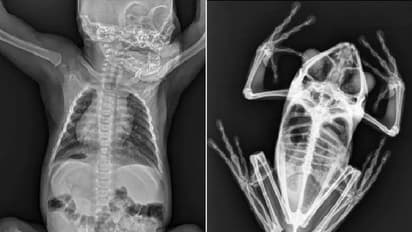

ഒരു നവജാത ഒറാങ്ങുട്ടാന്റെയും ഒരു തവളയുടെയും ആമയുടെയും എക്സ്-റേ ചിത്രങ്ങളാണ് അധികൃതർ സോഷ്യൽ മീഡിയയിലൂടെ പങ്കുവെച്ചത്. ഏറെ അമ്പരപ്പോടെയും കൗതുകത്തോടെയും ആണ് ആളുകൾ ഇതിനെ സ്വീകരിച്ചത്.